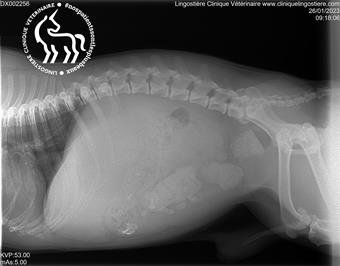

Distension abdominale

Identification et prise en charge des gonflements abdominaux anormaux chez le chien.

Cas cliniques en radiographies

Explorez nos diagnostics par imagerie à travers des cas concrets rencontrés au sein de la clinique.